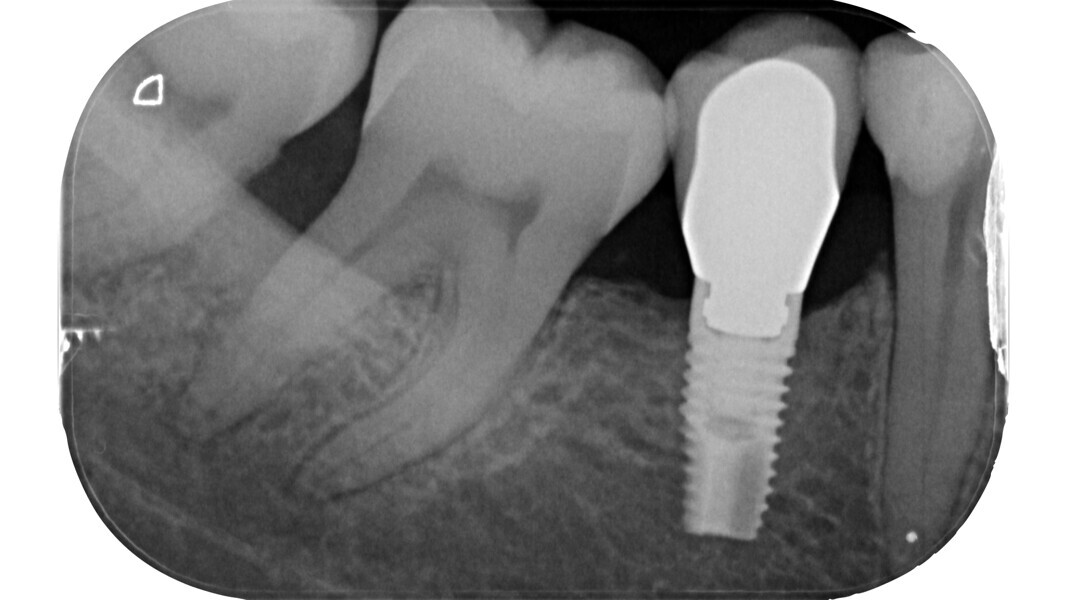

Fig. 13 : Emplacement des mesures effectuées par Deutsch et al.8, 9 sur une molaire inférieure analysée par micro-TDM (avec l’aimable autorisation du Prof. Elio Berutti).

Dans les molaires, la distance entre la pointe d’une cuspide et le plafond de la cavité pulpaire est d’environ 6,3 mm, tandis que dans les prémolaires supérieures, elle est de 6,94 mm. La cavité pulpaire a une hauteur d’environ 1,5 à 2 mm et la distance moyenne entre le plancher de la cavité et la furcation est d’environ 3 mm (Tableau 1) (Fig. 13).